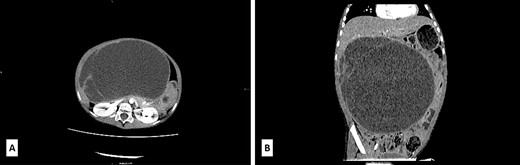

Case report

A 5-year-old boy presented with a 1-year history of abdominal discomfort and distension. Clinical examination by inspection and palpation revealed the presence of an abdominal mass that was confirmed by a CT scan. It revealed a multilocular cystic mass, with septations, filled with dense content (47−60 HU) and measured 113 × 190 × 195 mm3 (Fig. 1A). The lesion had an expansive growth but without clear liver infiltration (Fig. 1B). Differential diagnoses included mucinous cystadenoma, mesenteric lymphangioma, and hydatid cyst. A lung CT scan revealed a subpleural node in the right lower lobe, measuring 3.6 mm. Blood count test revealed elevated LDH levels of 391 U/L (range 100–190) and slightly elevated NSE level of 45.1 ng/mL (range 0–16.3) and CA 19–9 39.9 U/L (range 0–37), with normal levels of ferritin, AFP, CEA and β-HCG.

(A) Axial low-dose CT scan shows a huge cystic mass with few enhanced thin septa in the lateral aspect. Cystic space contains fluid of density 47−60HU. (B) Sagittal low-dose CT scan revealed that the cystic mass had expansive features with its cranial aspect not differentiated from the lower liver surface. No certain CT signs of liver infiltration were seen.